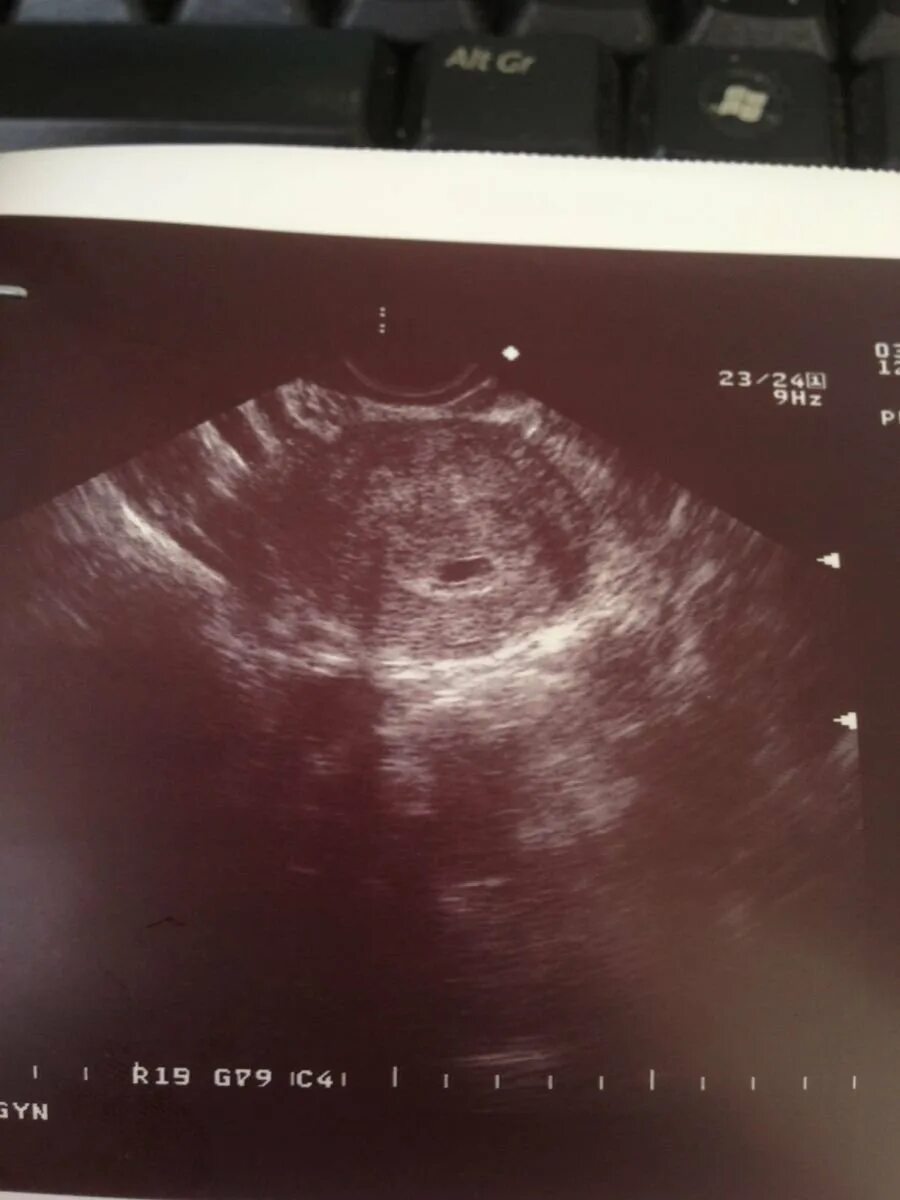

Плодное яйцо размером 3 3